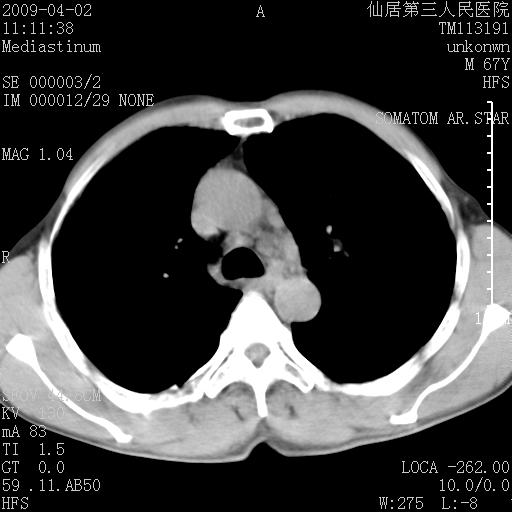

患者老年男性,乏力畏寒来诊,摄胸片示右下肺感染性病变,抗炎两周后复查胸片,无好转有进展。

后做ct平扫表现如下:

病灶呈蜂窝征,纵隔多个淋巴结肿大;肺泡癌需考虑